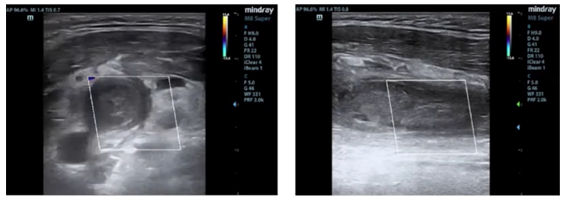

图2 患者颈部B超

门诊随访,定期复查颈部B超和胸部CT。